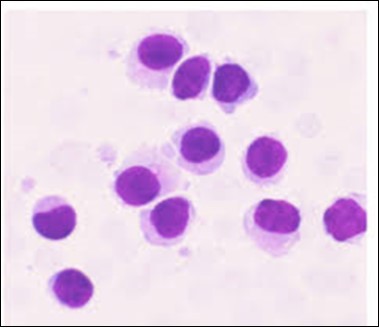

The classic hairy cell is medium sized with a magnitude of 10-14µm. The moderately abundant or variable cytoplasm may be transparent or mildly basophilic. The cellular surface with the characteristic serrated perimeter depicts innumerable fragile or stout extensions of cytoplasm ,particularly discernible on the phase contrast and electron microscopy. The cytoplasm may exhibit vacuoles with occasional azurophilic granules4. The nucleus may be elliptical or reniform, folded or indented with a coarse, reticulated or a finely dispersed chromatin and inconspicuous nucleoli along with infrequent mitosis. Bone marrow aspiration or bone marrow trephine biopsy may be inadequate for diagnosis in 30%-50% individuals4. The trephine sections of the bone marrow may depict a characteristic interstitial pattern of leukaemic infiltration. Generally the bone marrow is hyper-cellular, though it may be hypo-cellular in 10-15% individuals4. The leukaemia cell ingress may be diffuse or partial, although diffuse infiltration is frequent. The partial variety of leukaemic dissemination may be ineptly categorized with an indeterminate differentiation from the uninvolved marrow. The malignant insertions may initially emerge as miniature, undefined, cellular loci. The formalin fixed, paraffin embedded sections may elucidate a crystalline zone or a “halo” appearance of the cells with a circumscribed nucleus on account of the plentiful cytoplasm4. The cellular margins may be intertwined. Fixation of bone marrow smears with Zenker’s fixative may demonstrate a retracted cytoplasm of the hairy cells with a consequent disconnected structure. The bone marrow in the absence of a malignant process may be hypo-cellular or hyper-cellular. Reticulin stains may delineate an enhanced accrual of broad, dense reticulum fibres surrounding the aggregates of leukaemia cells with the fibrous circumlocution of individual malignant cell and fibrotic extensions into the abutting, uninvolved bone marrow4.

The leukaemia cells may enunciate a characteristic immune phenotype, crucial for a confirmatory diagnosis. The peripheral blood mononuclear B cell population may display a kappa or lambda light chain restriction. The phenotype of classic hairy cell leukaemia may be delineated by concurrent, immune reactive CD19+ CD20+,CD 11c+, CD25+, CD103+ and CD123+. An intensely immune reactive CD200+ and a non reactive CD27- antigen may be present2, 4. Evaluation of a trephine bone marrow biopsy and bone marrow aspirate may define the degree of tumour infiltration. A dry tap on account of prominent bone marrow fibrosis may be elucidated at preliminary diagnosis. A decline in the normal haematopoiesis may account for a hypo-cellular marrow in 10% instances. Gradation of cellular infiltrating of the leukaemia within the bone marrow may be appropriately investigated with immune –histochemical stains2, 4. Immune staining for CD20+, annexin 1 and VE1 (a BRAF V600E stain] may validate the diagnosis and precisely analyse the extent of malignant bone marrow infiltration[8]. Determination of BRAF V600E mutation may be critical in therapeutically non responsive individuals with applicable standard therapy or in instances of multitudinous reoccurrences[9]. Deploying inhibitors of BRAF V600E gene may be efficacious in patients impervious to approved therapy. The mutation necessitates a comprehensive scrutiny of the implicated individuals with a sensitive molecular assay which may discern up to < 10% of the hairy leukaemia cells appearing in the peripheral blood smears or bone marrow aspirates diluted with peripheral blood or aspirates elucidating a dry tap[2,4]. Allele specific polymerase chain reaction (PCR) or a next generation sequencing may be optimally employed to circumvent false negative outcomes. If the leukaemia cells are sparse or if particularly sensitive & efficacious molecular techniques are not accessible, the application of appropriate immune histochemical stains to the bone marrow biopsy such as a BRAF V600E mutation stain (VE1) may detect the hairy cells and conclusively diagnose the condition[2,4,10]. Figure 1, Figure 2, Figure 3, Figure 4, Figure 5, Figure 6, Figure 7, Figure 8, Figure 9, Figure 10, Figure 11, Figure 12, Figure 13, Figure 14.

Figure 4.HCL: hairy cells with widely spaced nuclei(20).

Figure 7.HCL: blebs on the cellular surface with fine nuclear chromatin(23).

Figure 13.HCL: hairy cells immune reactive for CD 11c(24).